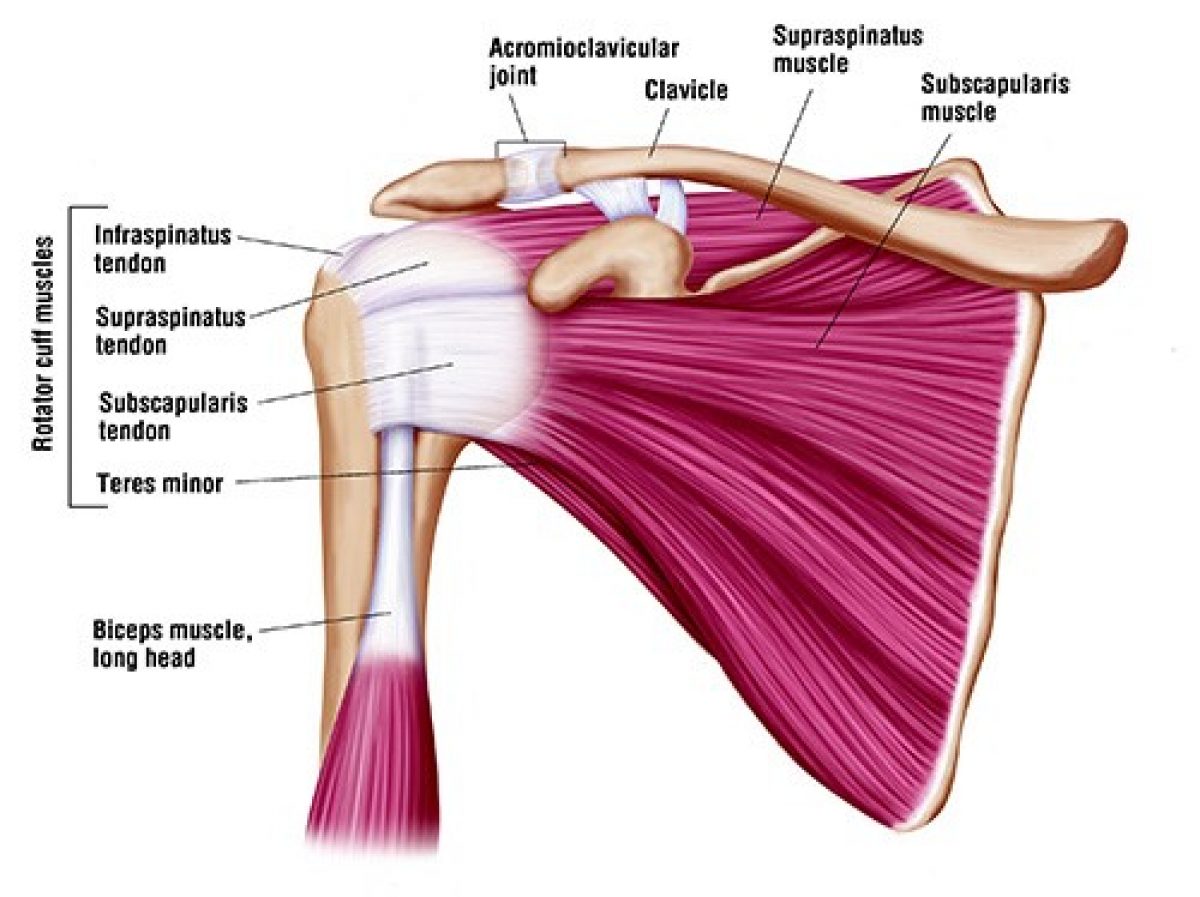

Фотографии мышц ротаторной манжеты плеча